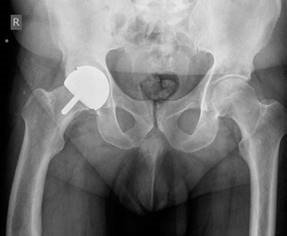

Questions in Trauma and Orthopaedics for the FRCS Section 6 Lower Limb and Pelvic Trauma Viva 41 This 27-year…